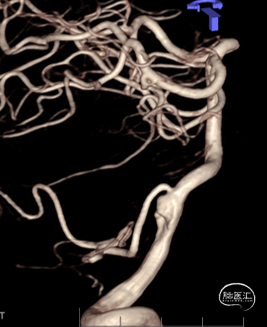

CTA:

右侧椎动脉(优势侧)V4段梭形动脉瘤,

左侧椎动脉纤细,后交通动脉未显影。

影像科提供的重建图像就像美颜照片,虽然好看,但丢失了诸多细节。

我们使用影像工作站重建的图像能够看到更多细节:

动脉瘤处有明显的凹陷,考虑为动脉夹层的内膜瓣;动脉瘤累及小脑后下动脉(PICA)的开口。